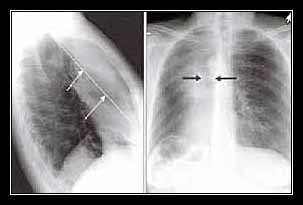

1. Chụp X-quang ngực

X-quang là công cụ đầu tay giúp phát hiện cơ hoành nâng cao bất thường, đặc biệt ở tư thế thẳng và khi hít vào-hít ra sâu. Tuy nhiên, chỉ có thể phát hiện rõ nếu liệt cơ hoành xảy ra một bên.